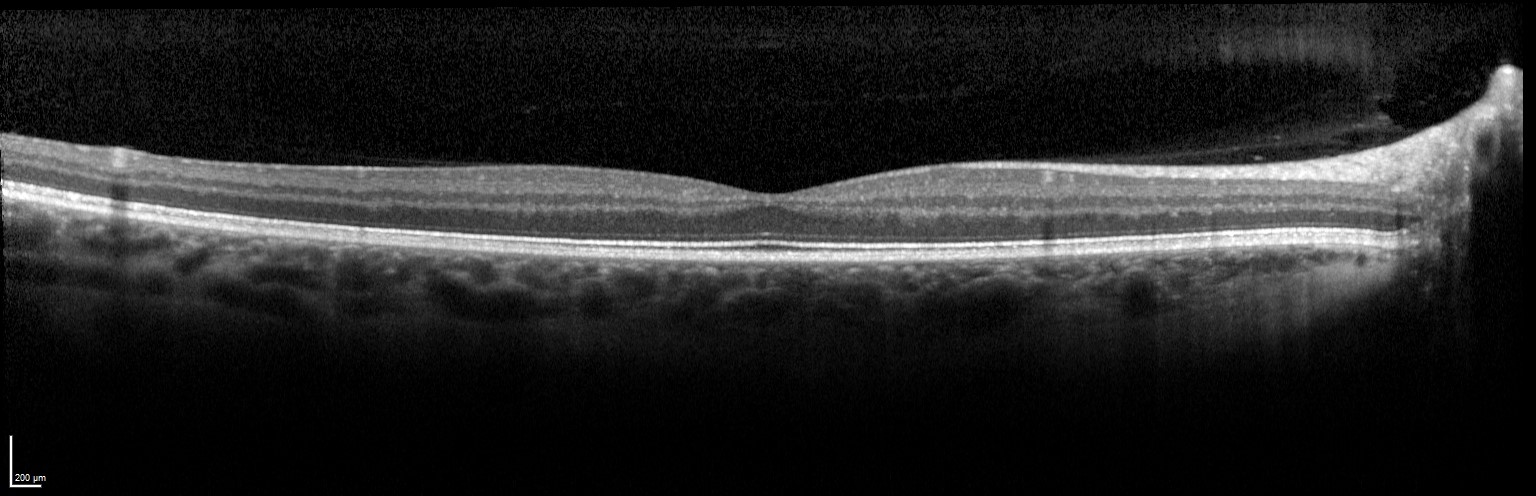

Spectralis OCT

The Spectralis OCT (Heidelberg Engineering, Germany) is a Spectral-domain optical coherence tomography device combined with scanning laser ophthalmoscope (SLO). It is a diagnostic device for high-resolution imaging of the retina, and with an extra module, also for the anterior segment.

DRI OCT Triton

The DRI OCT Triton is a combined anterior and posterior Swept Source OCT (ssOCT), which incorporates full colour high resolution fundus photography and fluorescence angiography.